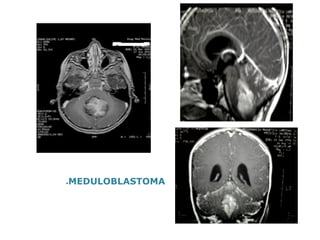

●MEDULOBLASTOMA

Casos Clínicos ●1)L.F.F, 6ª 7 m, ●Data da consulta: 13-08-2013 ●Procedente:Araçatuba –S.P ●Vômitos pós alimentares há 2 meses -> pediatra ->alt.da dieta +EDA ●40 dias -> cefaléiasúbita e intensa com melhora com analgésicos-.PS-> LCR !!!! ●35 dias -> desvio do olhar (estrabismo divergente)-> alteração do campo visual lateral bilateral ->NEURO ->RNM (19-07-2013 )-lesão em fossa posterior ●Marcha atáxica-> Ressecção macroscópica da lesão -> 6 dias com DVE-> chegou em mutismo + andando com apoio, porém com força preservada, sem SNE ●Diagnóstico:Meduloblastomaclássico totalmente ressecado –R0 M1-Alto Risco ●Neuro -eixo positivo LCR : negativo ●MO: negativa

MEDULOBLASTOMA E PNET ●Tumor de SNC mais comum na criança ; ●3-5 anos ; ●Subtipos histológicos: clássico ,desmoplásico(nodular),grandes células (anaplásico); ●Tendência a disseminação (1/3 ao diag) ●2 riscos: favorável x desfavorável (resíduo macro > 1,5 cm3e/ou meta SNC ou neuro-eixoe/ou LCR +) ●Fatores biológicos: c-myc,Trk, DNA ploidia, isocromossomo 17q ●Ttostandard: Cirurgia + QT+RT (p/ > 3 anos) ●< 3 anos: Cirurgia + QT , posterga –se RT